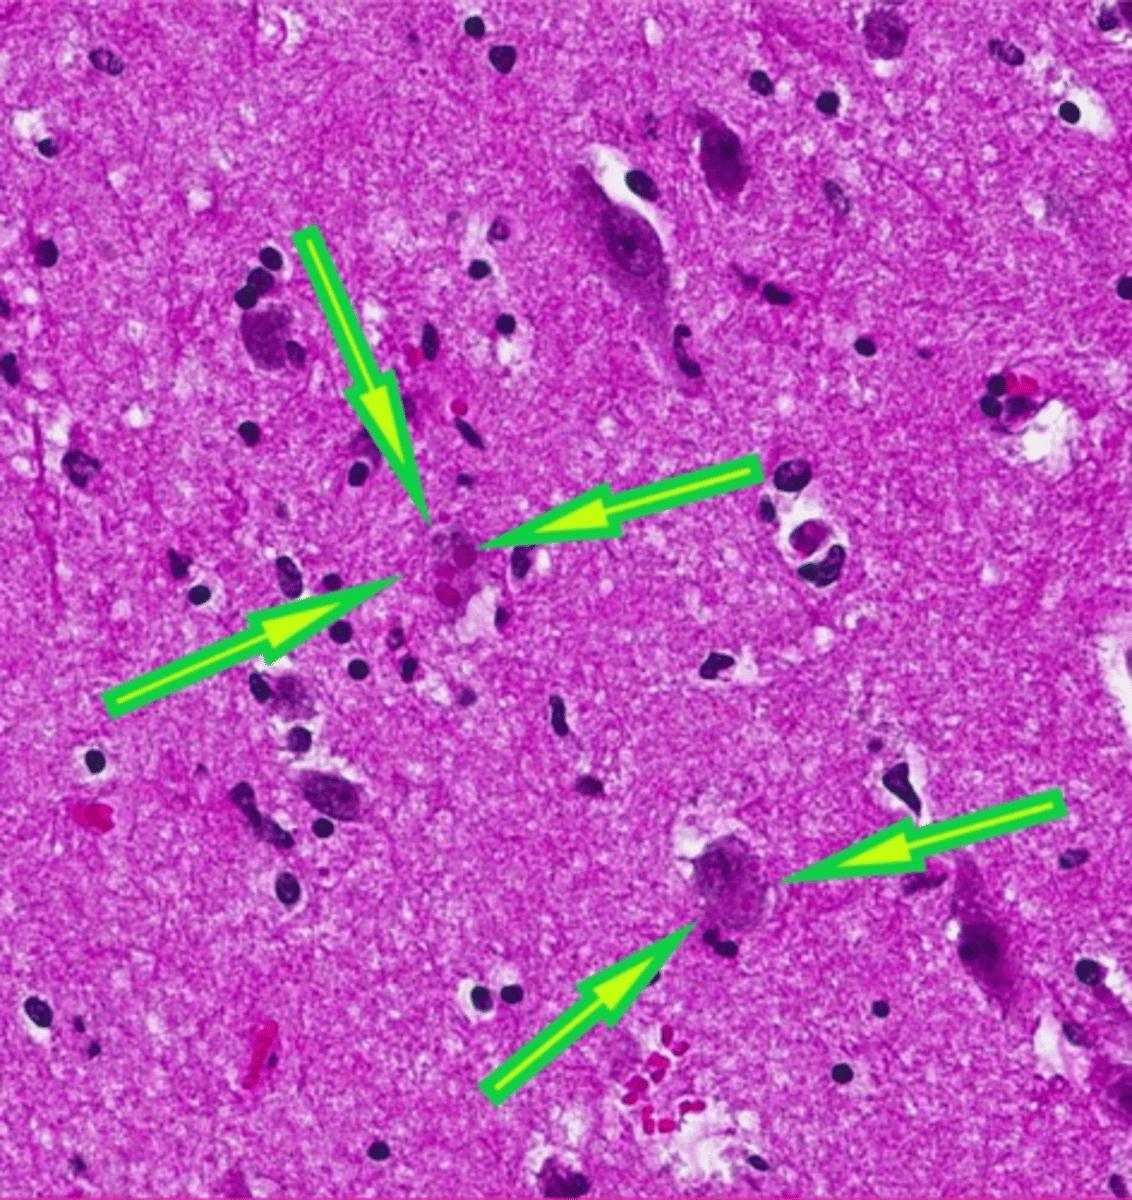

globoid cell leukodystrophy

What?